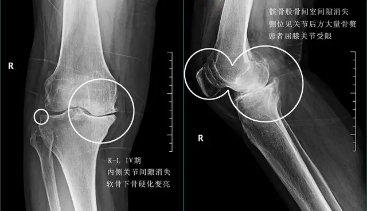

四期患者:4期的骨关节炎患者关节已经出现了严重的畸形,这个时期患者会非常的痛苦,关节会有严重的畸形,通常不能行走很长的距离,有一些患者甚至行走500米就疼痛难忍了。而且患者通常会出现比较明显的休息痛以及静息痛,什么意思呢?就是说,不动也痛。

此时我们只有通过进行关节置换手术的办法,才能帮助患者来解决痛苦。医生也知道很多患者不想做全膝关节置换术,所以说现在也研究出来单髁的置换手术,也算是一种保膝治疗。

以上x光的检查方式,只不过是比较初步的检查,可以帮助我们进行一个初步的诊断,对于关节内软骨韧带以及其他软组织的判断,最好的办法还是要依赖核磁。核磁可以非常早期的显示出关节内软骨磨损的程度以及是否出现了软骨下骨的硬化以及囊变,可以更准确的提供给医生需要的信息。比如像下图所示的这种髌骨外侧高压也是骨关节炎的一种,但是排x光片可能并不会像核磁能显示出这么清晰的软骨改变。